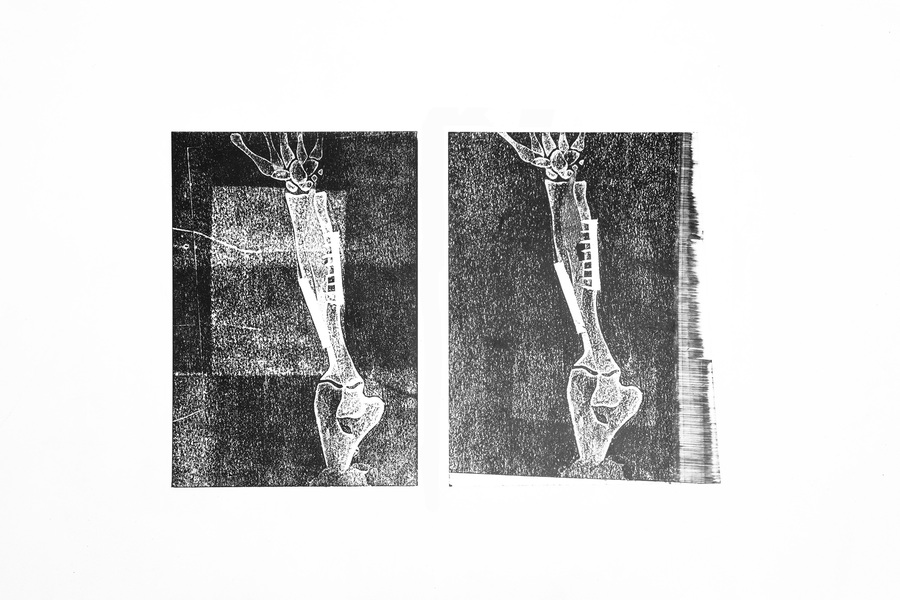

С развитием медицины все больше людей могут позволить себе импланты или металлические конструкции, помогающие работе костей и мышц. Это становится инородным телом внутри человека, что особенно заметно на рентгене. На снимках эти приспособления имеют белый цвет, что значительно отличается по цвету от остальных органов и скелета. Я решила подчеркнуть эти замененные части человеческой опорно-двигательной системы с помощью печати. Для имитации рентгеновского снимка я использовала прозрачный пластик.

Серия состоит из трех работ и выполнена в технике высокой печати. В работе использовалась черная типографская краска и листы прозрачного пластика. Формы для печати вырезались из переплетного картона. Для оформления понадобились белые рамки, светодиодные ленты и листы матового пластика. Все работы выполнены в формате A3.

Итоговая серия